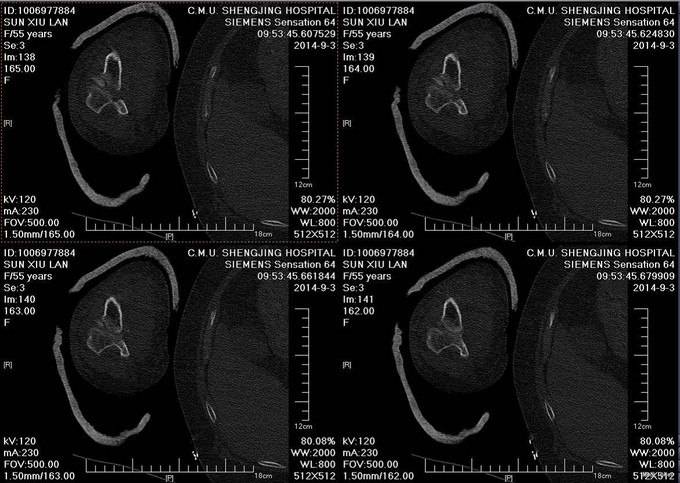

主诉:摔伤后右肘部疼痛10小时 患者自述2014-9-2 早8点自己走路时不小心摔倒,右肘部着地,导致右肘部疼痛、肿胀、活动受限,于当地医院拍片诊断为“右肘关节脱位”,给予手法复位, 为求进一步治疗来我院,诊断为“左肘关节骨折”,并收入我科,患者自受伤以来,无发热,无呼吸困难,无腹痛腹泻,饮食睡眠正常,大小便未见异常。

患者步入病房,左肘关节肿胀明显,压痛(+),骨擦音及骨擦感(+),左上肢感觉未见异常,左手指活动正常,左桡动脉搏动可触及。

患者入院后左肘关节石膏固定,左肘关节对症消肿等治疗。1周后完善检查后查无明显手术禁忌症后行左桡骨小头骨折切开复位内固定术。